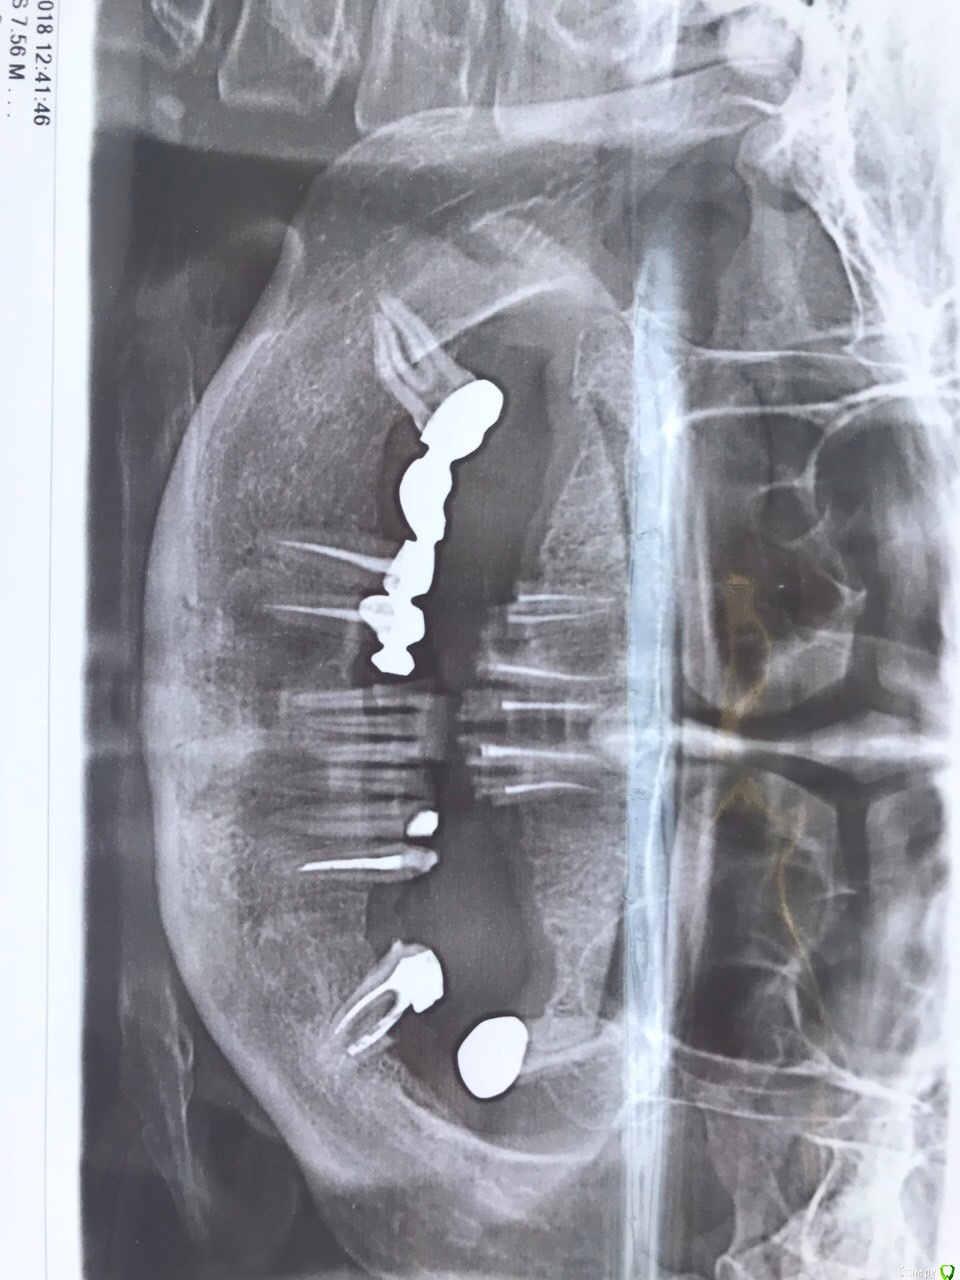

dr.Dre Опубликовано 27 марта, 2018 Поделиться Опубликовано 27 марта, 2018 Добрый день ,помогите пожалуйста с планом лечения,передние 4 хочу под вкладки коронки ,какие имлпанты ставить ,на в/ч у пациентки был бюгель на замках сейчас планируется не съёмная конструкция. Ссылка на комментарий

dr.Dre Опубликовано 27 марта, 2018 Автор Поделиться Опубликовано 27 марта, 2018 Как понять вопрос-какие импланты ставить?извините неправильно написал ,сколько поставить чтоб была несъёмная конструкция? Ссылка на комментарий

Irouil Опубликовано 27 марта, 2018 Поделиться Опубликовано 27 марта, 2018 4-5-7 до семёрок или 4-6 до шестёрок. Итого 4 или 6 всего Ссылка на комментарий